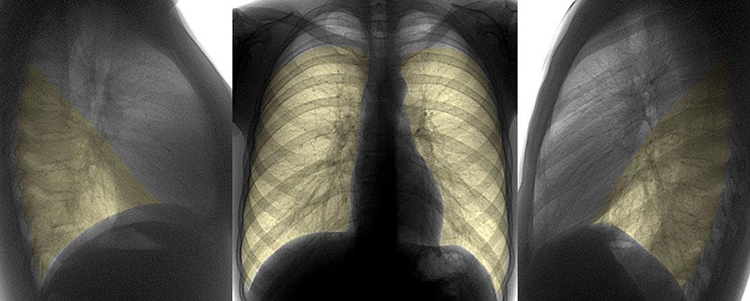

• рентгенограмма органов грудной полости в прямой и боковой проекции;

Рентгенограмма органов грудной клетки

рентген легких

Рентген – пневмония

• Рентгенография грудной клетки. На снимке при пневмонии обнаруживается гомогенное затемнение воспаленных участков.